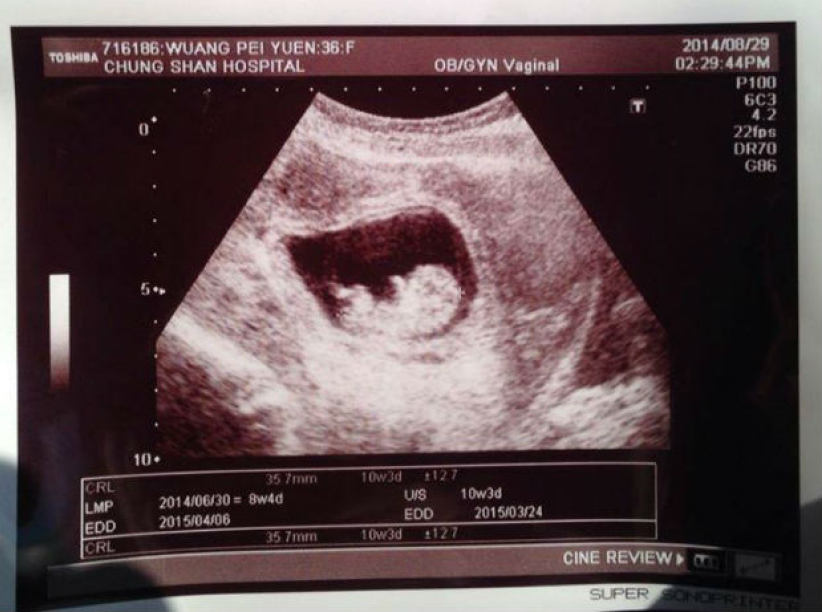

他貼上太太接受檢查以及超聲波下胎兒的照片,並寫道:「我們又有了!上帝給的超過所求所想,數字週刊拍到我們產檢,說我的精子會轉彎,我只能說感謝上帝,祂給的超過所求所想,請跟我們一起期待家中的新成員...!」

壹週報導提及王婉霏五年前曾發現長了6顆子宮肌瘤,醫生曾表示她可能會不孕,沒想到不單止生下兩個可愛孩子宇恩 及「小泡芙」,現在再傳喜訊,令人驚喜。